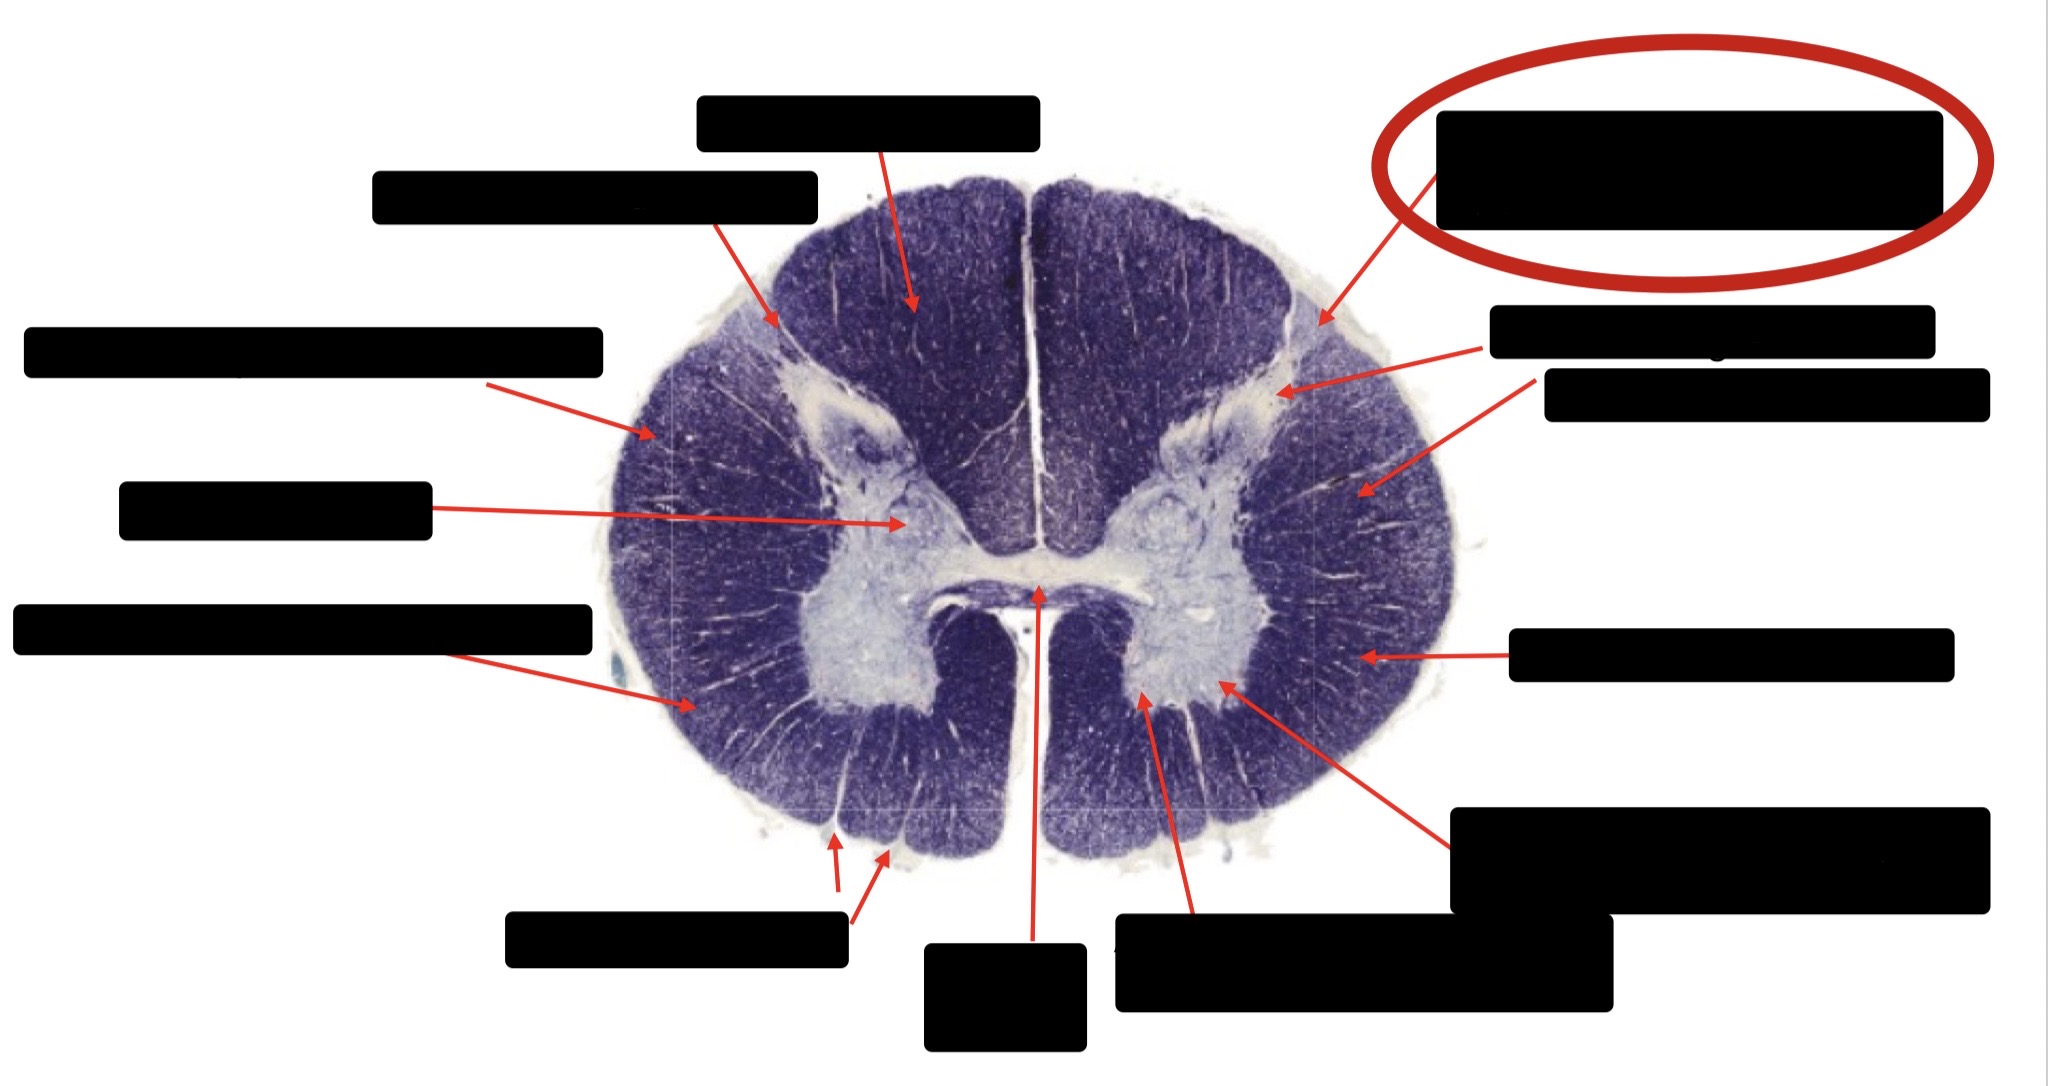

Spinothalmic Tract

Central Canal

Posterior Column (Fasciculus Gracilis)

Large Fiber Entry Zone

Lissaeur’s Tract & Small Fiber Entry Zone

Substantia Gelatinosa

Lateral Corticospinal Tract

Ventral Root Fibers

Anterior Horn Motor Neurons

Anterior Medial Fissure

Dorsal Rootlet

Posterior Spinocerebellar Tract

Anterior Spinocerebellar Tract

Posterior Column (Fasciculus Cuneatus)

Anterior Horn Motor Neurons (Distal Muscles)

Anterior Horn Motor Neurons (Proximal Muscles)

Anterior Corticospinal Tract